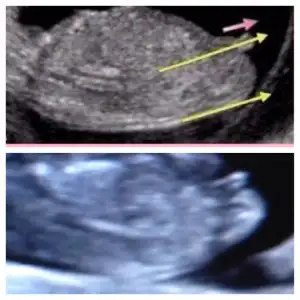

dr soylemeden siz gorun genital nub teorisi ( bebegin cinsiyeti)

Cnm ben mı yanlıs bakıyorum acaba herkeste görüyorum kendıme görrmıyormuyum ki acaba ya offf bana paralel gelıyor baksana alttakı benım bebısım usttekı ınternette Nub fotosu bu fotoda 11 haftalık tı bebegım suan 12+5 oldumBence nub. Ve erkek bu bebis galuba.. cunku kordon olsa daha yukarda olur .. kac haftalik ?

Canm ben boyle cızdım paralel geldı ama yanlışmı bakıyorum acaba alttakı benım bebısErkeğe daha çok benzettim ben canım. Yukarı doğru açılı duruyo.

Baksana ben mı yanlıs bakıyorum canmCanim nub u paralel evet kiz olabilir..bizim ki bi tahmin..kesin olamaz..hayirli olsun canim bebeisin

Banada yorum yaparmisiniz ben kiza benzettim.. peki sizzz???